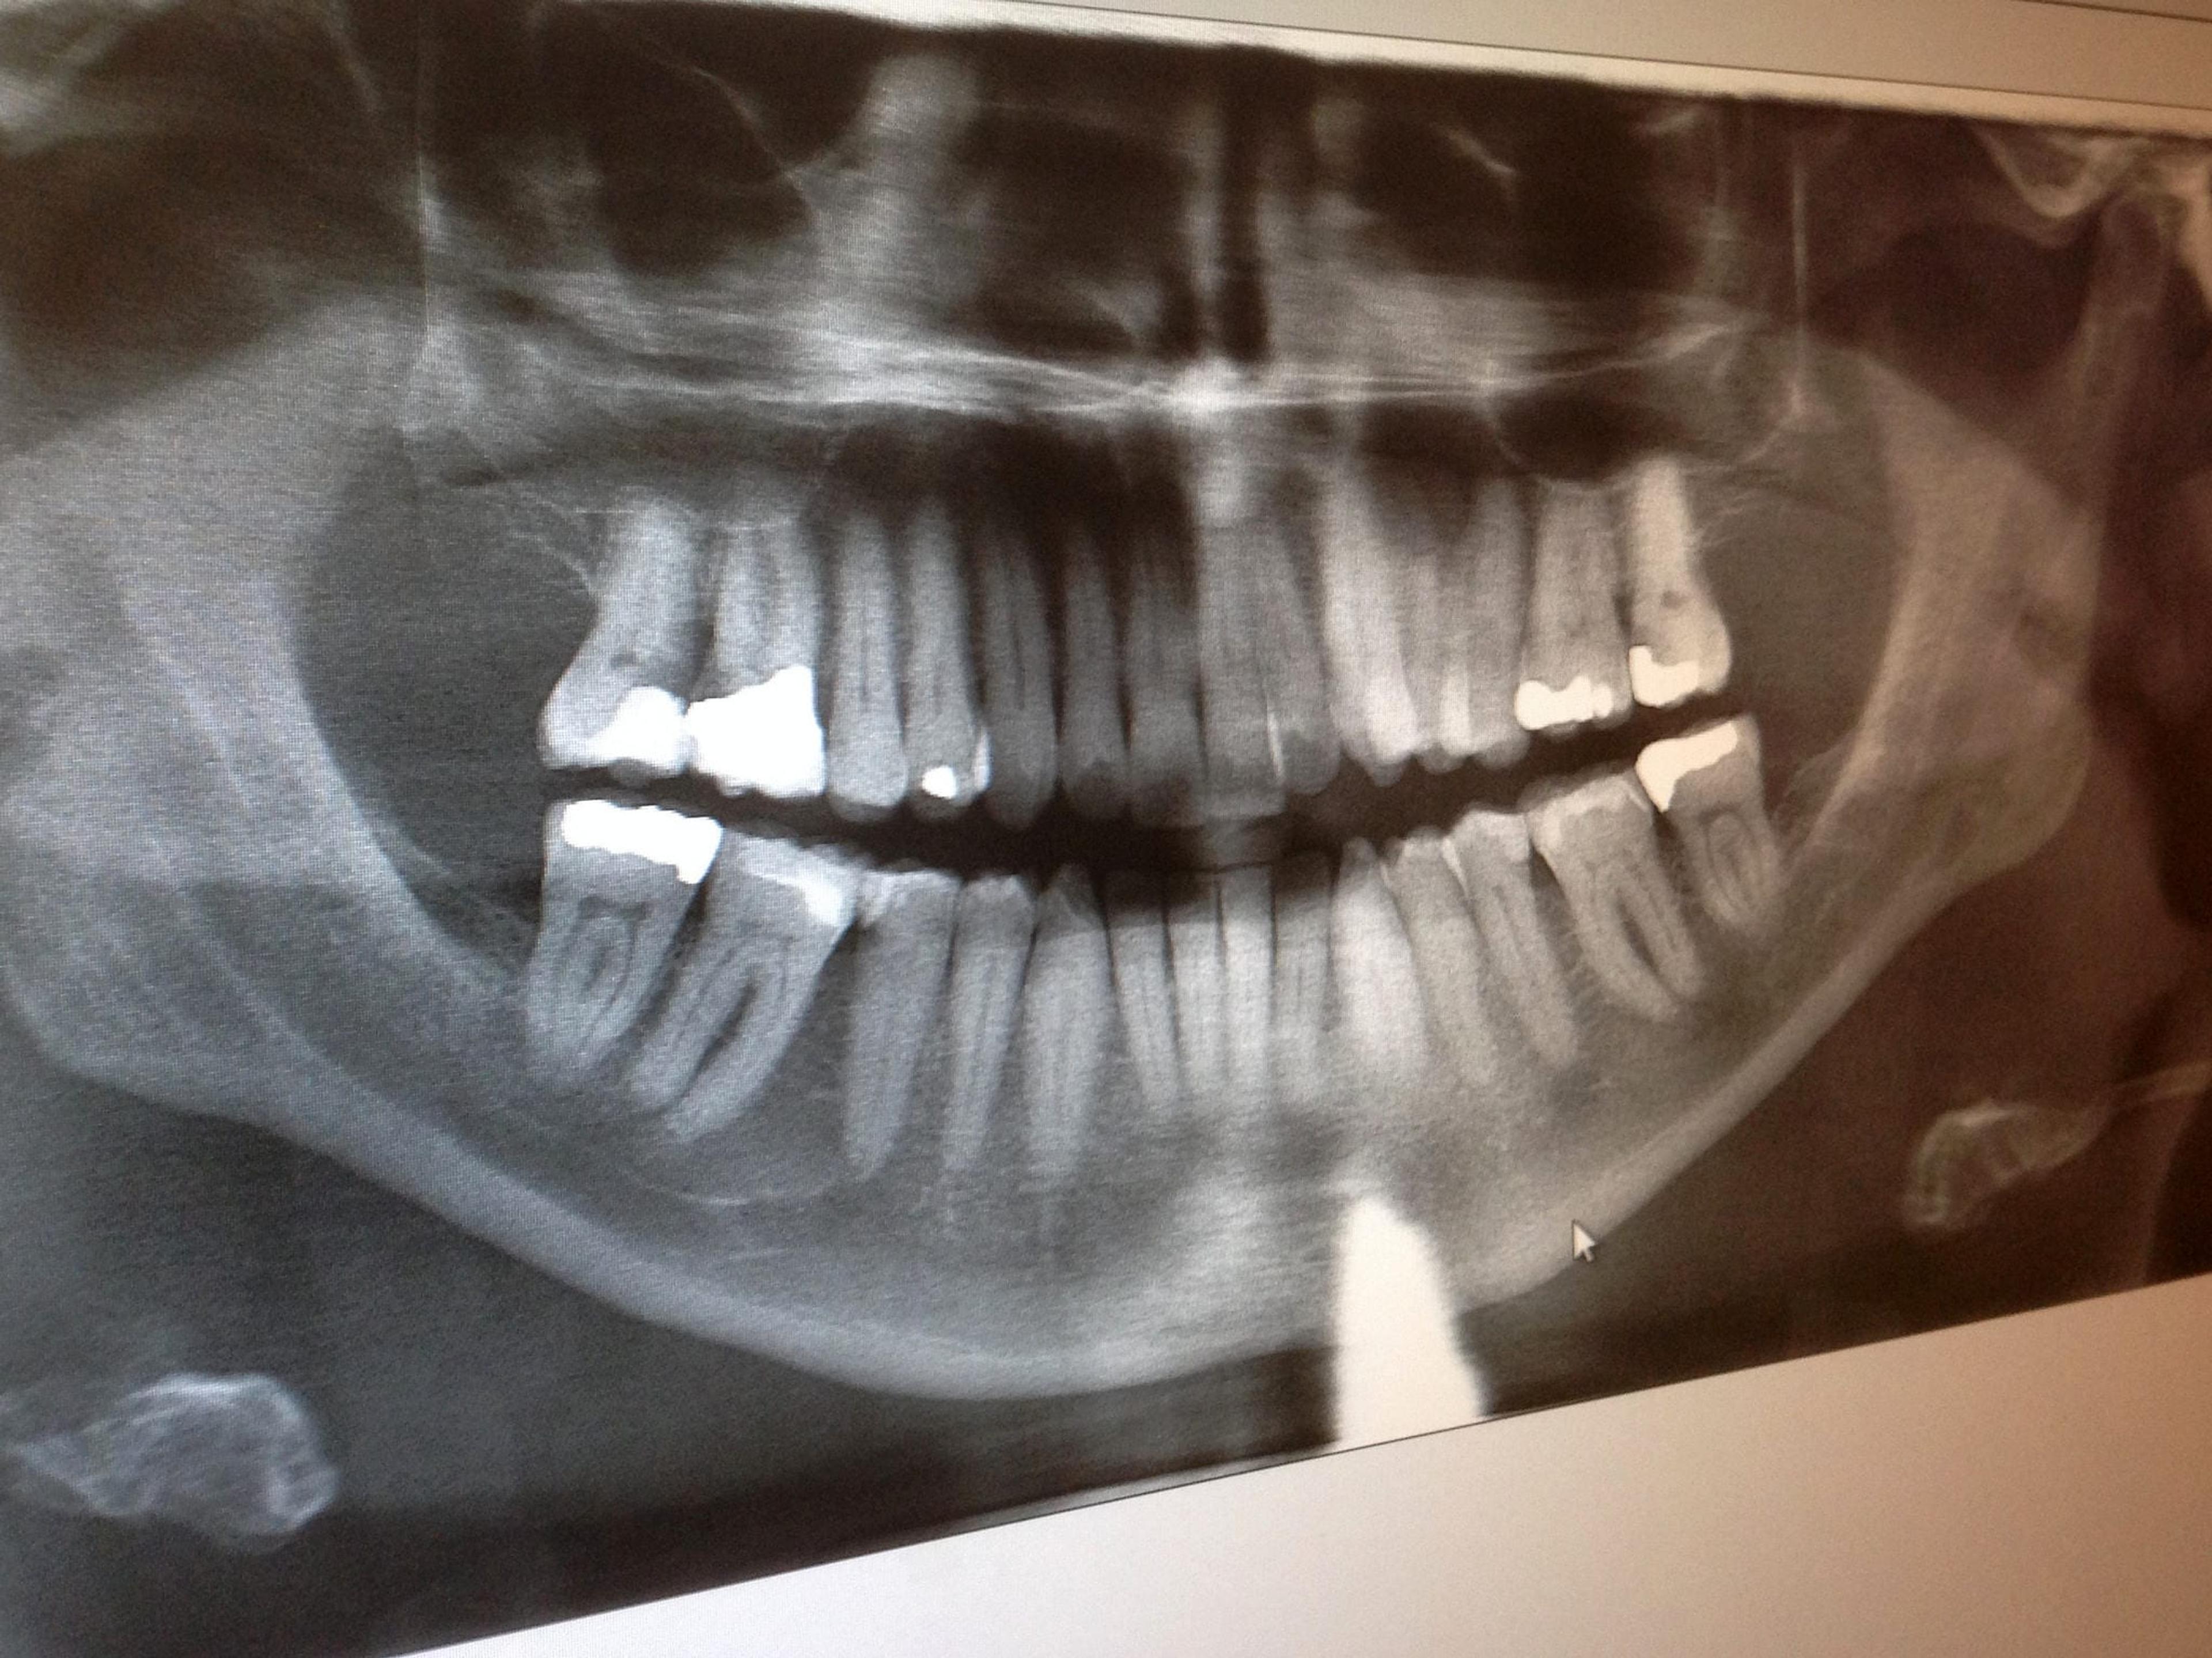

Imagine being unable to eat or having to miss work because of severe mouth pain caused by a lack of access to dental care. Those are just two of the anecdotal patient cases from the first Superior Dental Day held in 2016. Both patients were treated free of charge and reported positive oral health results moving forward. A volunteer-driven effort, Superior Dental Day returns on Saturday, April 15 at the West Ishpeming Dental Center, which provides space for the event free of charge. Staff volunteer their time as well, along with many other local dentists and hygienists – 35 total are scheduled to participate, taking shifts to accommodate 65 registered patients. Another 30 patients are on the wait list, which highlights the need for services. The program is the brainchild of the UP Area Health Education Center, (UP AHEC) based out of Northern Michigan University in Marquette. The team at UP AHEC, Cindy Noble, executive director, Lisa Hyde, executive secretary, and Carole Touchinski, program manager, have been busy securing funding and volunteers for the second annual event. Blue Cross Blue Shield of Michigan is a financial supporter. When registration opened for residents of Marquette, Alger and Baraga counties in late February, slots filled up in less than two days. Touchinski said the opportunity to have oral health issues addressed is appealing for people who haven’t been able to access traditional dental services. She said oftentimes people might be working two part-time jobs that don’t offer insurance or don’t make enough to feel like they can afford care. “What we are seeking to do is help those individuals who kind of fall between the cracks of the social support programs that are out there and available to some,” Touchinski said. Because many programs already exist for children, Dental Day is just for adults. Appointments are available to uninsured or underinsured adults with incomes that fall at or below 200 percent of federal poverty guidelines. Clients receive dental assessments, x-rays and cleanings and can get fillings or even have teeth pulled if necessary. Touchinski said some registered patients called with really significant pain they need taken care of. “This allows them an opportunity at least to get some of that pain addressed so that they are more able to live comfortably, with dignity and take the next steps necessary to improve their lives,” she said. Fixing dental problems and helping people get healthy from an oral perspective restores dignity, Touchinski explained. They leave feeling better and are also equipped to carry through on new habits. Basic dental hygiene techniques are covered during the appointment and a nutritionist works with patients to help them understand how their dietary habits could be negatively affecting their oral health. Patients are also presented with different community resources they might be able to take advantage of regarding their teeth or other health and personal needs. “We’re trying to do the best we can hooking up the clients to continued services before they leave the door that day,” she said. Volunteer dental professionals do what they can for patients in the time they have. If a serious problem is identified, say a patient needs a root canal, they’ll be referred to dentists that might be able to help them by offering payment plans. Touchinski said several patients at last year’s event developed a rapport with their assigned dentist and were able to continue treatment with them after the day was done. Overall, Touchinski said dental services are a high need in the Upper Peninsula. She points to Alger County, which only has limited oral health care availability. Depending on where you live and where the closest office is to you, a dentist appointment could take up an entire day when you factor in the time to drive there and back. Touchinski said with the success of Dental Day, she’s hopeful that the model will expand to other communities so that more people can be served. For patients with appointments last year, it was a major confidence boost. “They were very thankful and very grateful,” she said. If you liked this post, you might also enjoy: